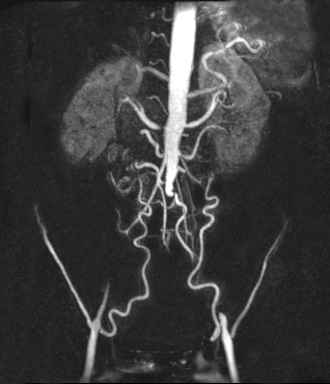

Die MR-Angiographie ist ein bei uns regelmäßig eingesetztes modernes strahlenfreies Untersuchungsverfahren zur Darstellung der Schlagadern und der Venen. Hierdurch können beispielsweise Verengungen der Blutgefäße (Stenose) in allen Körperregionen erfasst werden. Damit ist diese Technik eine der besten Methoden die Ursachen einer eingeschränkten Gehstrecke (Schaufensterkrankheit) zu untersuchen. Die MR-Angiographie ist auch sehr gut geeignet um pathologische Gefäßerweiterungen (Aneurysma), z.B. der Bauchschlagader, zu erkennen oder um angeborene Varianten der Venen und Schlagadern zu untersuchen. Die Untersuchung der großen Körpervenen erlaubt es Blutgerinnsel (Thrombose) oder angeborene Engstellen der Venen (z.B. May-Thurner Syndrom) zu erkennen. Ständige Verbesserungen der Gerätetechnik haben die Aussagekraft der MR-Angiographie soweit verbessert, dass auf eine weiterführende invasive Katheterdiagnostik oft verzichtet werden kann. Die MR-Angiographie ist ein Standardverfahren um die Behandlung von Gefäßkrankheiten zu planen.

Typische Untersuchungsgebiete für die MR-Angiographie sind:

• Bauchschlagader (Aorta)

• Nierenarterien (A. renalis)